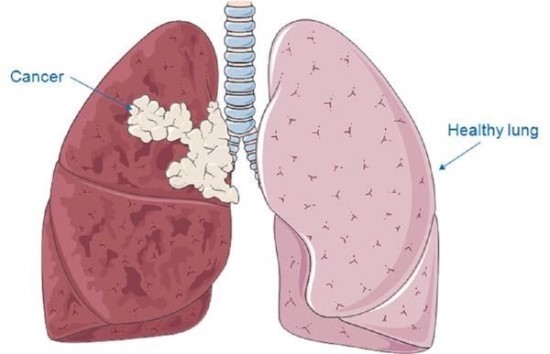

오늘은 우리 몸의 호흡을 책임지는 폐에 대해 이야기하려 합니다. 특히, 폐에 발생하는 악성 종양인 폐암의 초기 증상에 대해 자세히 알아보려 합니다.

폐암 초기에는 특별한 증상이 없는 경우가 많지만, 암이 진행되면서 다양한 신호를 보낼 수 있습니다. 다음은 폐암 환자들이 흔히 경험하는 10가지 주요 초기 증상입니다.

- 설명: 붉은색이나 녹슨 철 색깔의 피가 가래에 섞여 나오거나, 심한 경우 기침할 때 피만 나오는 증상입니다. 이는 폐암이 혈관을 침범했을 때 나타나는 중요한 경고 신호입니다.

가슴 통증

- 설명: 폐암이 흉벽(가슴 벽)까지 침범하면 찌르는 듯한 통증이나 둔하고 지속적인 통증이 발생할 수 있습니다.